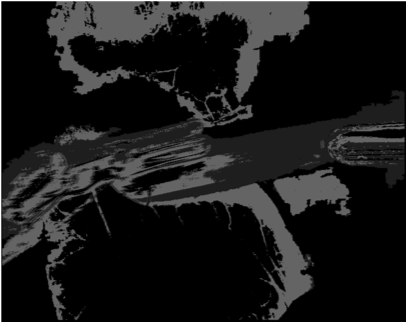

Our challenge was made up of 3 sub-problems. The first was binary instrument segmentation, where each frame was separated into da Vinci Xi instruments and a background class, which contained an ultrasound probe, surgical clips and porcine tissues. The second task was instrument part segmentation, where we scored the participants on whether they could correctly segment each articulating part of the instrument (see Fig. 3). Our final task was to segment and classify the instruments (see Fig. 4).

We provided the first 225 frames of 8 sequences as training data and kept the last 75 frames of those 8 sequences as test data. 2 of the full 300 frame sequences were kept as test sequences. Test labels were kept hidden from the participants. Our datasets contain 7 different robotic surgical instruments. The Large Needle Driver, Prograsp Forceps, Monopolar Curved Scissors, Cadiere Forceps, Bipolar Forceps, Vessel Sealer and additionally a drop-in ultrasound probe, which is typically held in the jaws of the Prograsp Forceps instrument. Samples from the training datasets are depicted in Fig. 2 and examples of the different instrument types are shown in Figure 3 and 4.